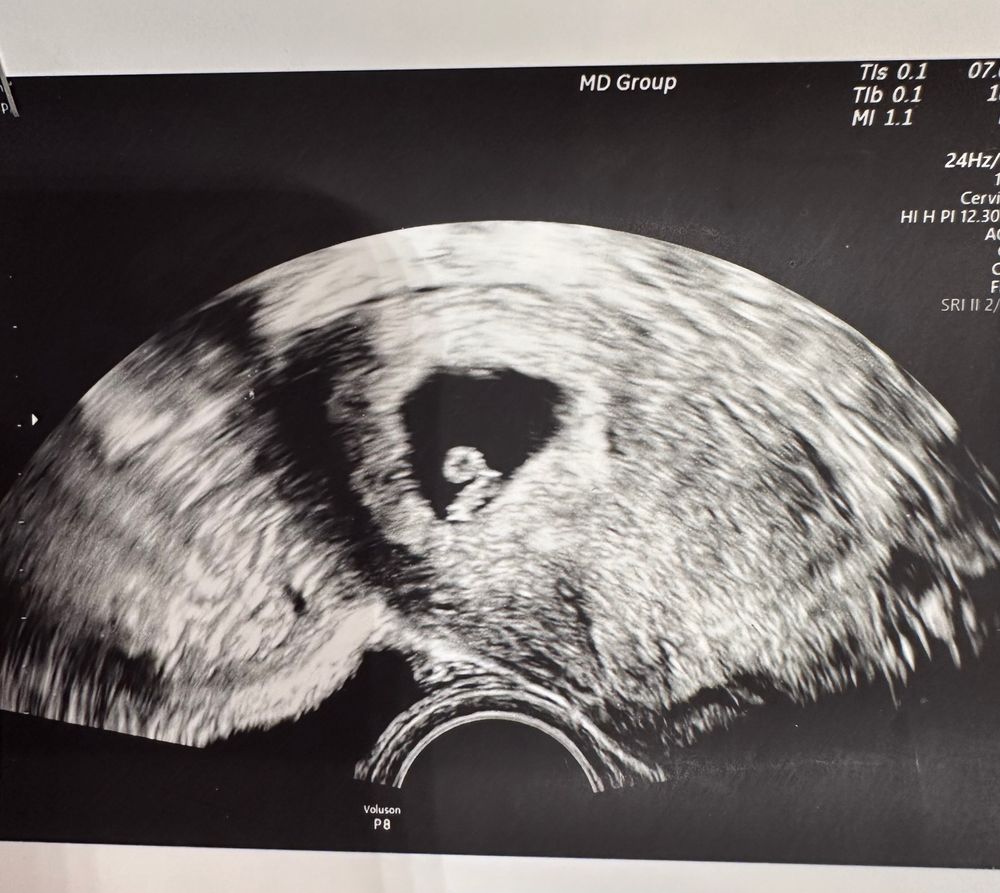

Сегодня все было отлично. Но все равно уже поехали на УЗИ.

У нас все отлично. 4АВ растет,сердце стучит и все у нее отлично. Сегодня попросила позвать супруга,чтоб посмотрел на СБ. Первый раз видела,чтоб так внимательно изучали монитор)))

Запомнила,что КРТ 5,1. ЖМ 4,5. А ПЯ,кажется,20. Но как обычно репродуктолог все занесла себе,а мне таких подробностей не пишет 😂